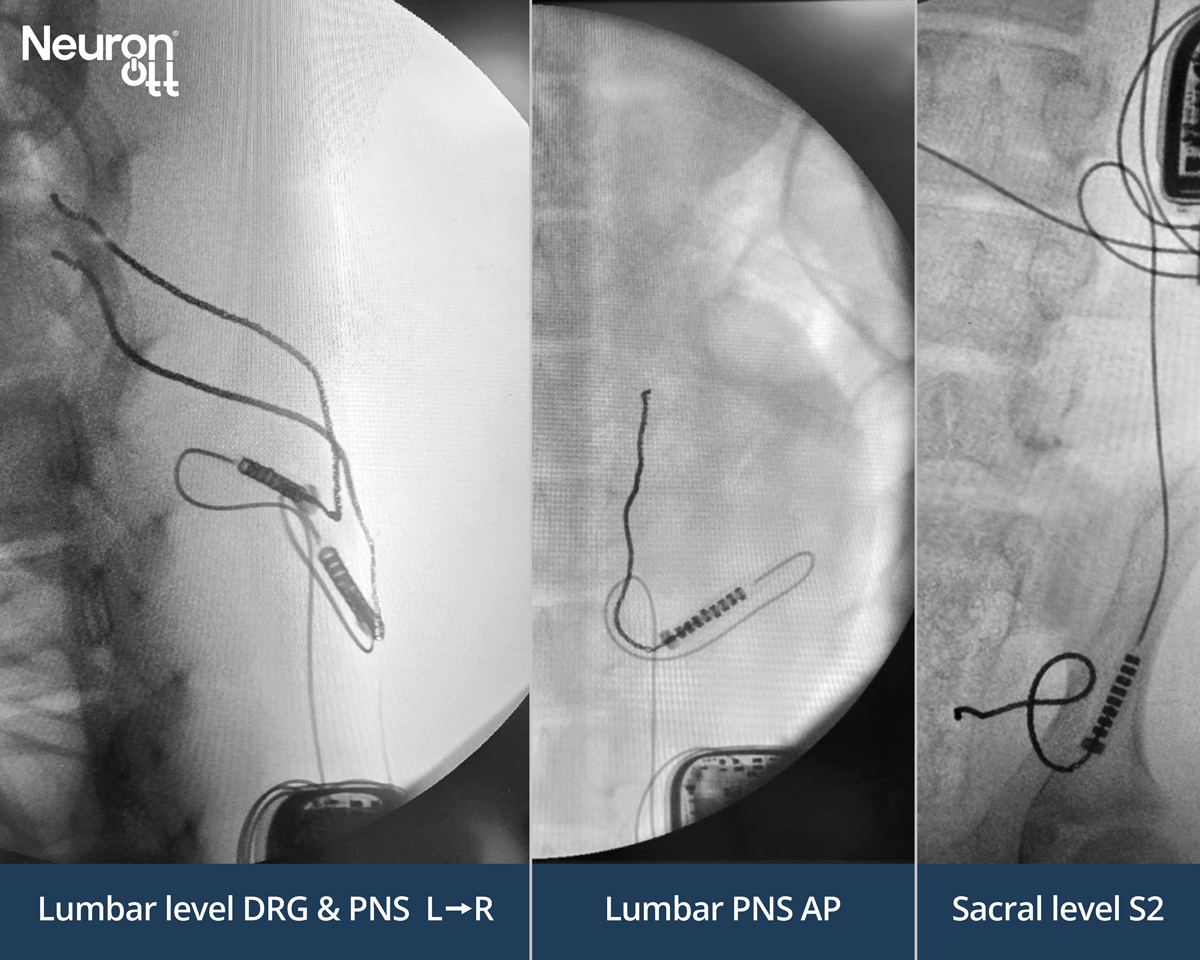

Needle-Delivered Tripolar Electrode Connects to Standard IPG Connectors; Selectively Stimulates Lumbar DRG, Peripheral Nerve, and Sacral Targets from Single Implantable Pulse Generator

Neuronoff Announces Safety and Functionality Success in First-in-Human Trial of Injectrode for Minimally Invasive Chronic Pain Relief (LIFE study)

The company has successfully completed the first-in-human clinical trial evaluating the safety and effectiveness of its flagship product, the Injectrode, designed to treat chronic pain

This milestone in chronic pain management involved two study participants receiving the minimally invasive injectable electrode, targeting peripheral nerve branches in the lumbar lower back — a key area for novel lower back pain treatments.